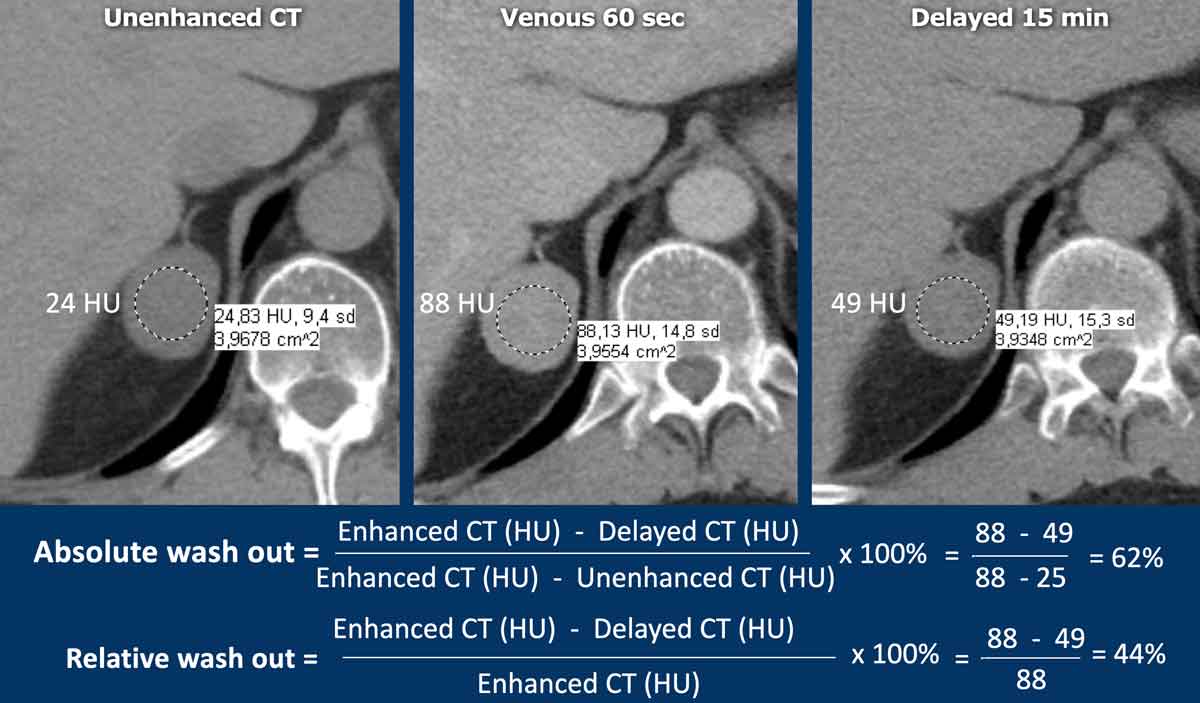

A dedicated adrenal washout CT protocol consists of a non-contrast, a contrast -enhanced scan with a delay of 60-90 sec and a delayed scan at 15 minutes.

The ROI should encompass at least 2/3 of the lesion to ensure a representable assessment.

Absolute enhancement wash out ⩾ 60% is proof of an adenoma [5,6,8].

Relative washout

If an adrenal lesion is discovered on an enhanced scan while the patient is still on the table, then a second scan of the adrenals at 15 minutes after contrast injection can be made and the relative washout can be calculated.

Relative enhancement wash out ⩾ 40% is proof of an adenoma [5,6,8].

The images show an indeterminate lesion on the nonenhanced CT (density 24 HU).

The absolute washout in this patient is 62%.

This means that the lesion is a lipid-poor adenoma.